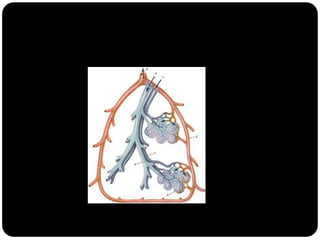

Lóbulo pulmonar secundário

Menor porção do pulmão, ainda circundada por um septo de

tecido conjuntivo;

Composto por 3 a 5 bronquíolos terminais (3 a 12*)

Identificado na TCAR tanto em estados normais quanto

patológicos;

Revestidos por septos interlobulares que contém as tributárias das

veias periféricas e dos vasos linfáticos;

 Ácinos pulmonares: porção do pulmão distal a um

bronquíolo terminal e consiste dos bronquíolos respiratórios,

dos ductos alveolares, dos sacos alveolares e dos alvéolos;